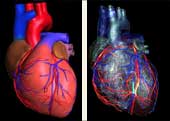

Kardiovaskularne bolesti su ubica broj jedan u današnjem svijetu i odnose svake godine više života nego sve maligne bolesti zajedno. Koronarna bolest je najčešće uzrokovana aterosklerozom (stvaranjem plakova u zidu krvnih žila uzrokojući njihvo suženje). Donedavno, nije postojao neinvazivni način da se direktno analiziraju koronarne arterije na prisustvo aterosklerotskih promjena. Razvoj tehnologije višeslojnog CT-a (MSCT/MDCT) omogućio je detaljno trodimenzionalno prikazivanje kucajućeg srca u toku jednog zadržavanja daha. U našem dijagnostičkom centru nudimo ovu tehniku pregleda koronarnih arterija, na multi-slice aparatu, s najmodernijim softverom i minimalnom dozom zračenja.

Šta je CT koronarografija?

To je metoda prikaza malih arterija koje hrane  srčani mišić, upotrebom CT skenera, koji prikazuje protok krvi u koronarnim arterijama i kompjuterskog softvera da bi se dobio odgovarajući trodimenzionalni prikaz. CT angiografija je neinvazivni način da se prikažu zidovi koronarnih arterija I nadju eventualni aterosklerotski plakovi, što pomaže liječniku u odredjivanju rizika srčanog udara.